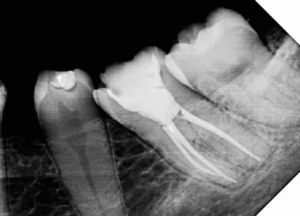

Alguns trabalhos